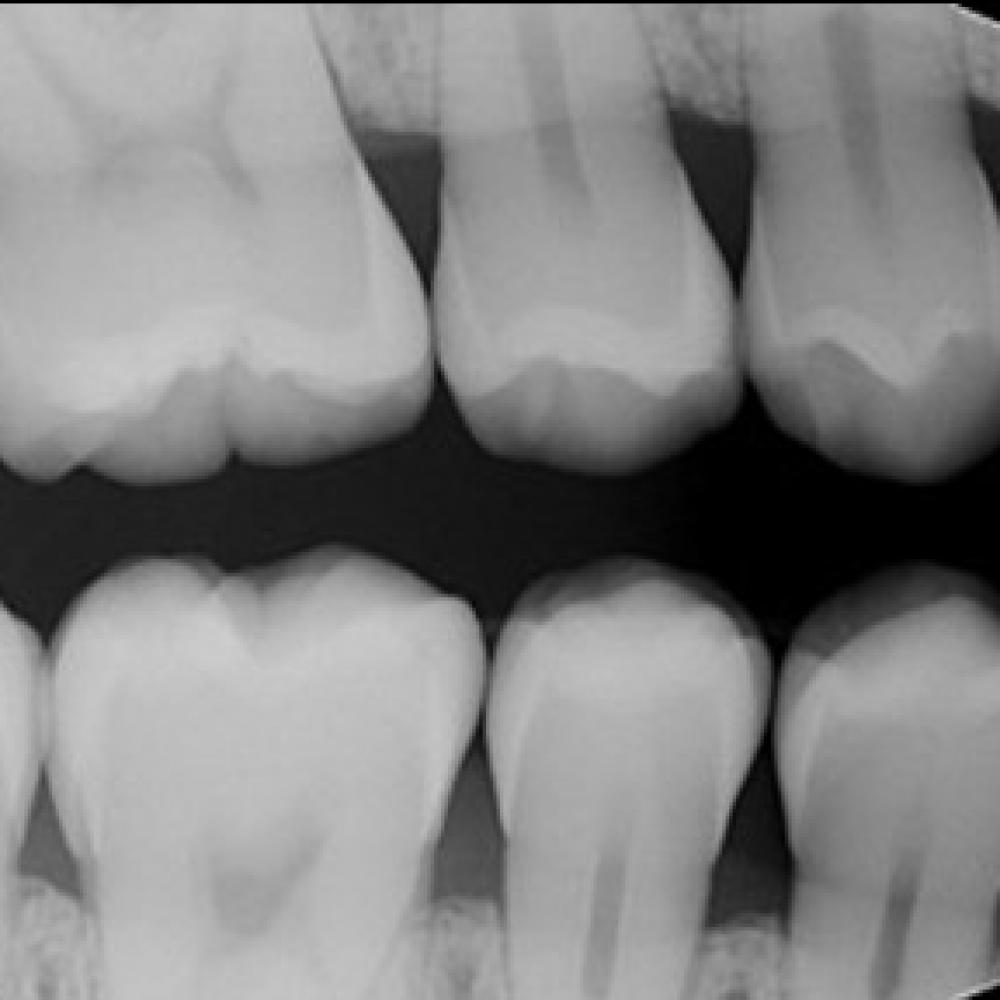

Digital x-rays, often referred to as digital radiography, are the very latest in dental xray technology. Digital x-rays utilise a digital image capture device rather than x-ray film. This system saves time as there isn’t any need to develop film photographs and produces pictures with a better resolution than standard dental x-ray machines. Digital x-rays also send out significantly lower levels of radiation as pictures are produced electronically.

Digital x-rays can be used to diagnose:

• Decay between teeth

• Poor tooth and root positions